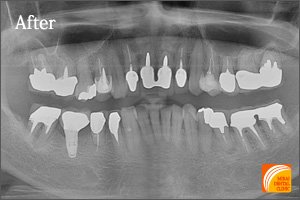

症例4

Before

期間 :5カ月

回数 :6回

費用 :1,155,600円

内容 :インプラント3本、GBR、セラミック冠3本分含む

After

上の歯1本、下の歯2本インプラントを埋入した患者さんです。患者さんのご希望通り、前後の歯を削って歯に負担をかけるブリッジや、違和感があり、こまめな清掃が必要な部分入れ歯を回避できます。